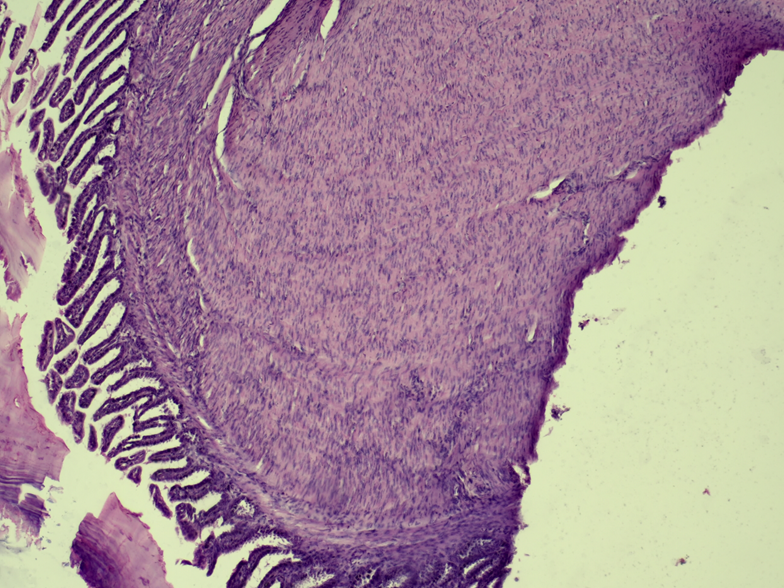

The radiographic study did not refer conclusive results. Post-mortem evaluation revealed small intestine with marked wall thickening. In serial sections of the small intestine stained with hematoxylin-eosin (H&E), a thickened longitudinal muscular tunic was evaluated, with palisade proliferation, slightly disorganized, of parallel spindle cells with a central nucleus and homogeneous eosinophilic cytoplasm (Fig. 1 & 2). Lamina propria and submucosa with marked congestion in blood vessels. No mitotic figures or cellular atypia were observed. Histopathological diagnosis referred intestinal leiomyoma.

Figure 1: Small Intestine. Muscular tunic with dense, non-encapsulated erosion of smooth muscle fibers. Mucosa without histological alterations. H-E. 20x

Figure 2: Small Intestine. Longitudinal muscular tunic with proliferation of smooth muscle fibers and compression of the submucosal tunic. H-E. 40x